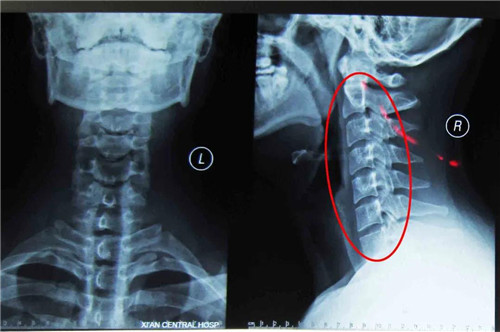

王女士所患颈椎病类型是当下年轻人中最为常见的一种——颈型颈椎病。

颈型颈椎病又称局部型颈椎病,X线片上没有椎间隙狭窄等明显的退行性改变,但可以有颈椎生理曲线改变、椎体间不稳定及轻度骨质增生等变化。不少反复落枕的病人即属于这种改变,是最早期的颈椎病,也是治疗最为有利的阶段。